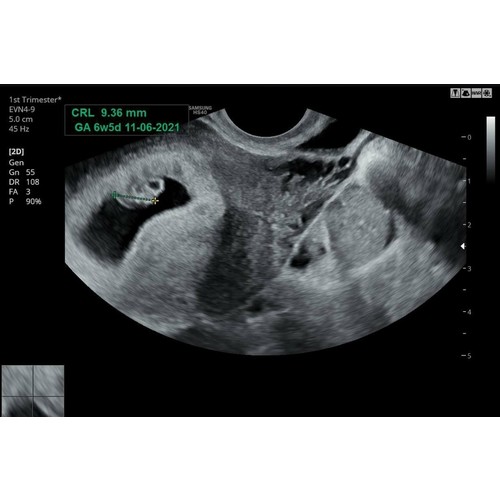

Bij 6+5 weken 9,36mm, ze zei wel dat ze het niet heel precies kon meten dus kan ook iets minder of meer zijn geweest.